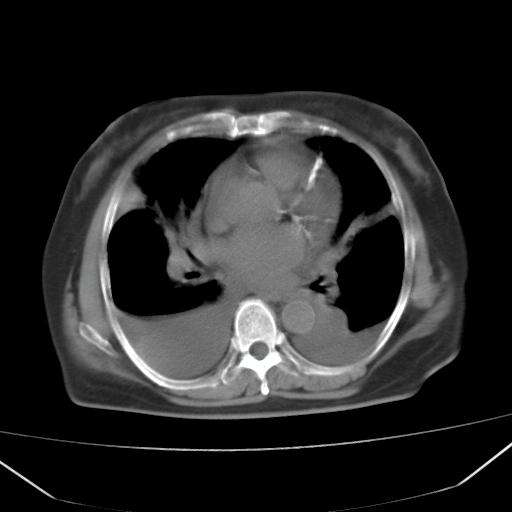

以下是引用liuyue在2008-4-19 22:25:00的发言:[br]先考虑:1.心衰伴肺水肿、双侧胸腔积液、叶间积液、双下肺不完全性肺不张; [br] 2.冠状动脉粥样硬化。

以下是引用lijuanln在2008-4-19 23:05:00的发言:[br]两侧胸腔积液,肺水肿[br]心包积液[br]提示心衰

以下是引用jiangjing在2008-4-20 10:43:00的发言:[br]结合病史支持 冠心病[冠状动脉钙化],心功能不全,肺淤血、肺水肿,双侧胸腔与斜裂积液